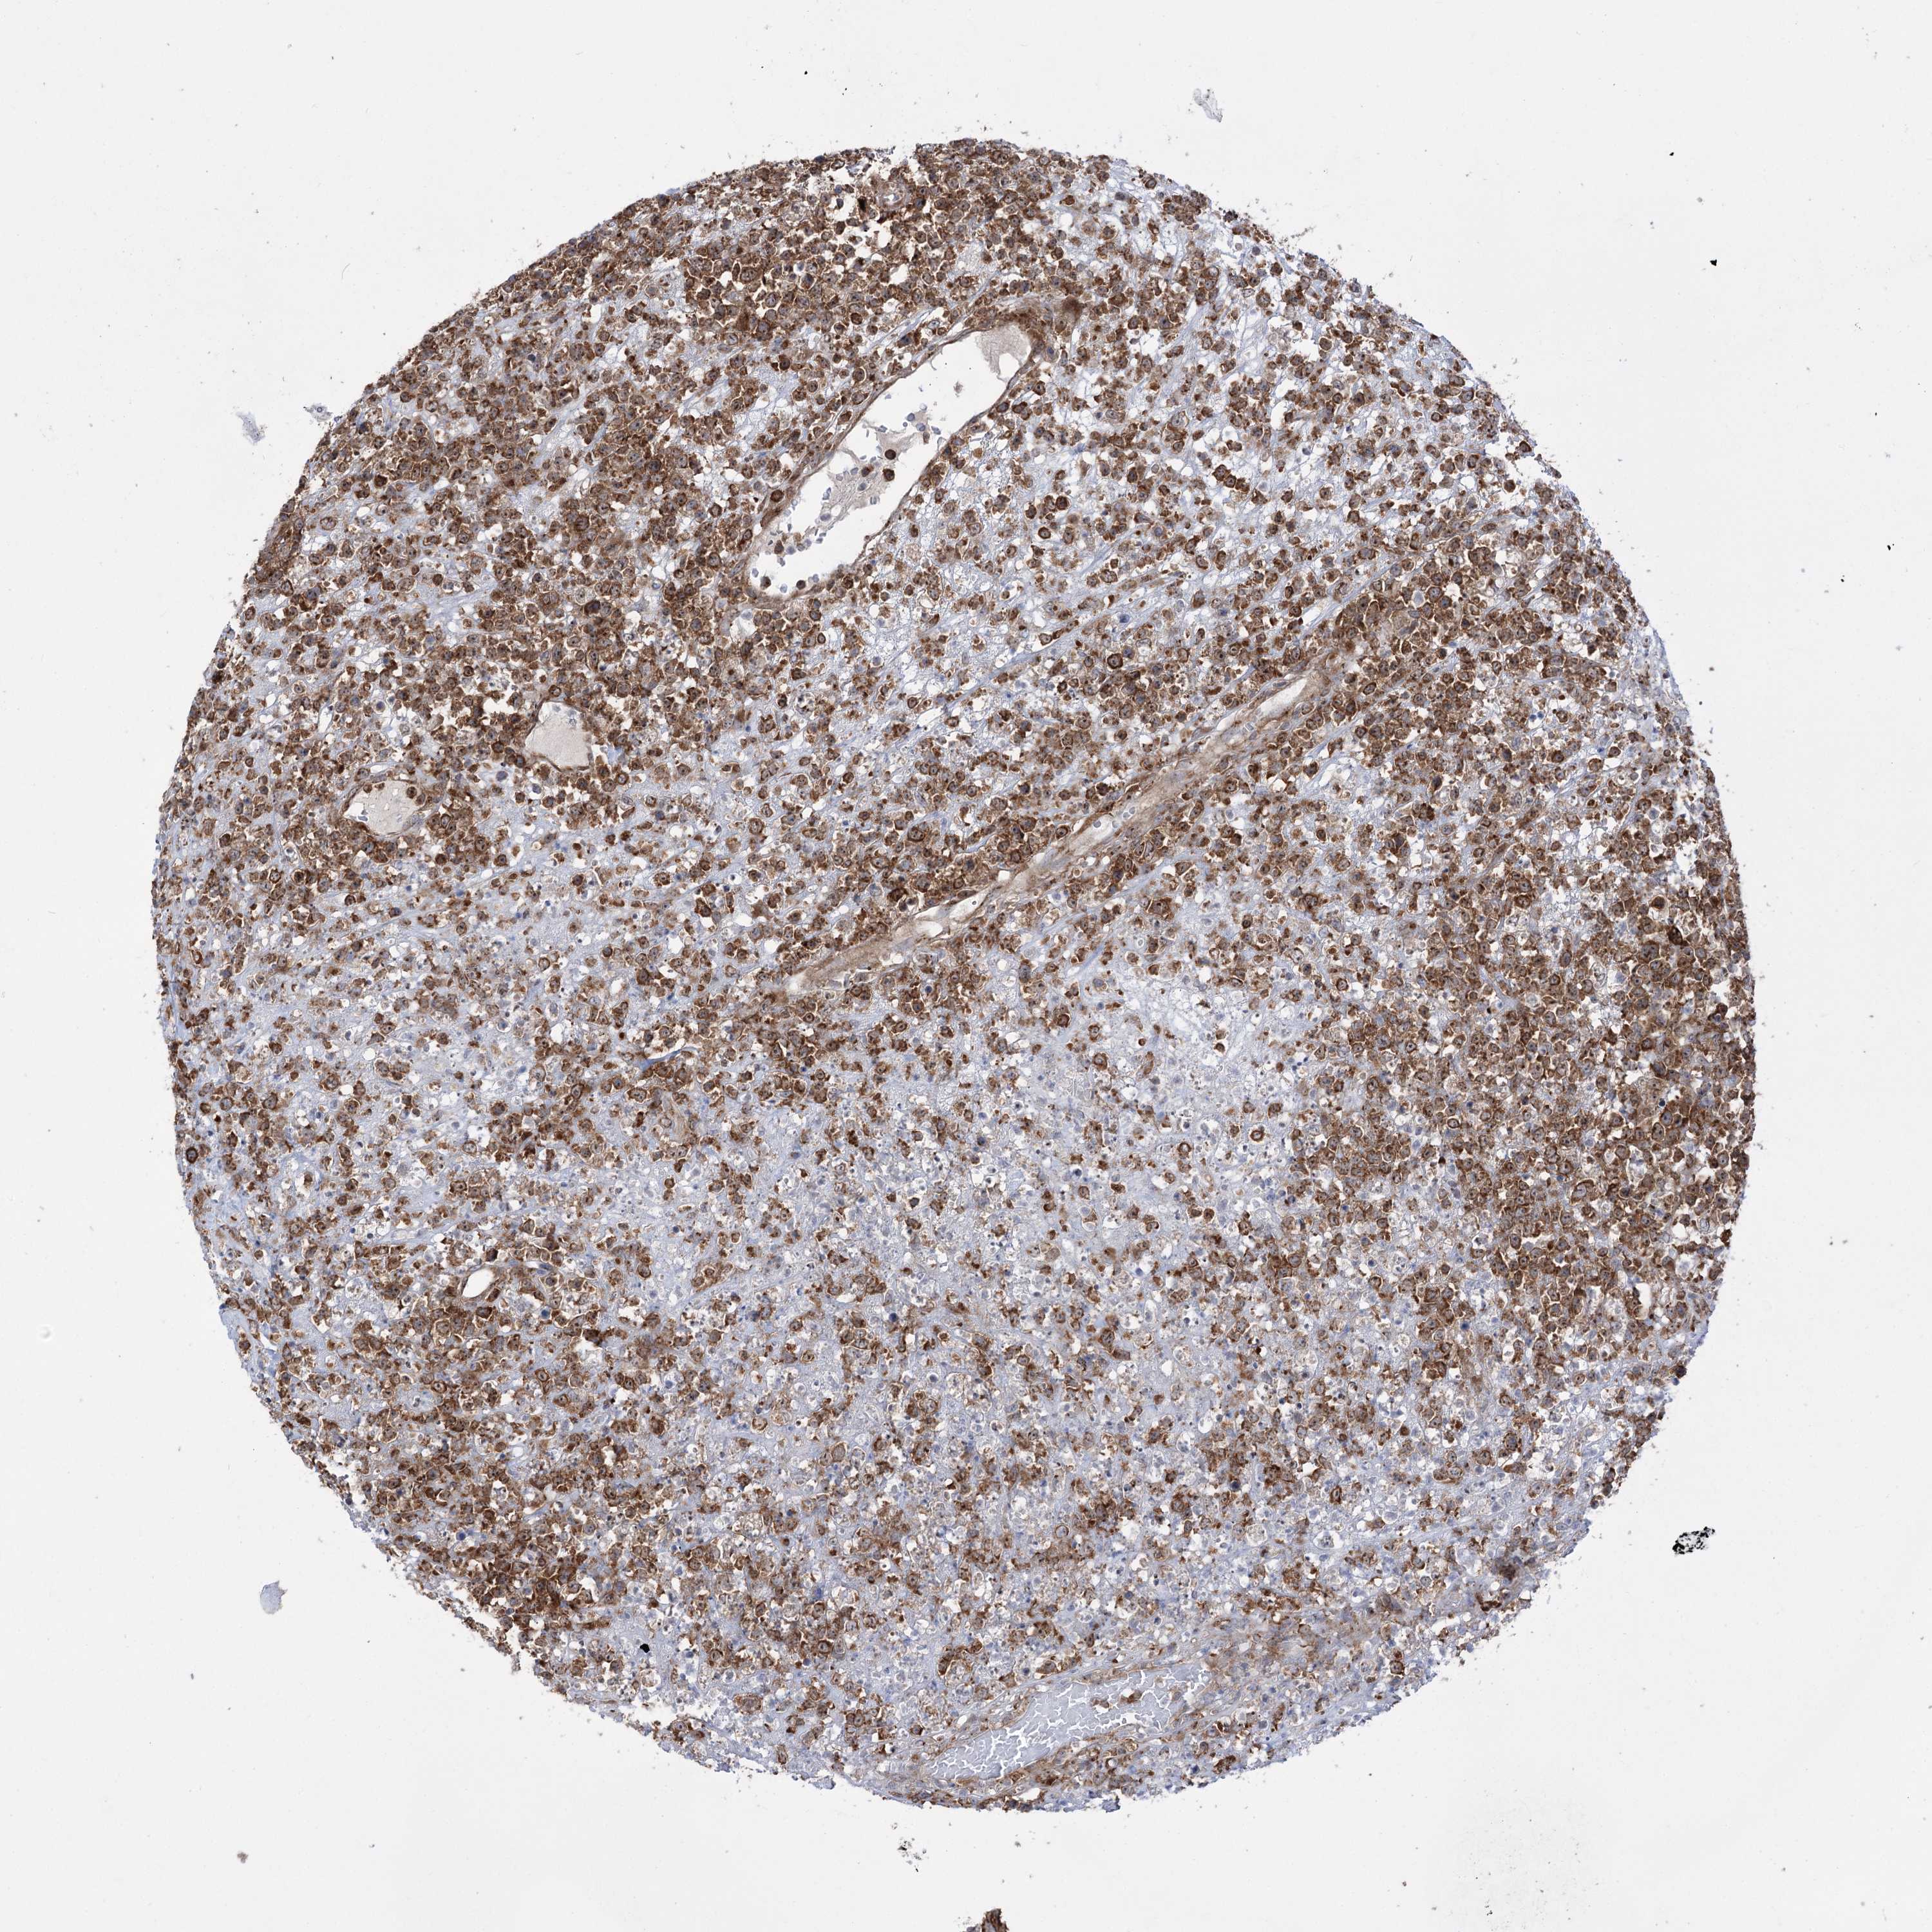

LYMPHOMA - Protein expressioni

A mouse-over function shows sample information and annotation data. Click on an image to view it in a full screen mode. Samples can be filtered based on level of antibody staining by selecting one or several of the following categories: high, medium, low and not detected. The assay and annotation is described here.

Antibody stainingi

Antibody staining in the annotated cell types in the current human tissue is reported as not detected, low, medium, or high, based on conventional immunohistochemistry profiling in selected tissues. This score is based on the combination of the staining intensity and fraction of stained cells.

Each image is clickable and will lead to virtual microscopy that enables deeper exploration of all samples and also displays staining intensity scores, fraction scores and subcellular localization as well as patient and tissue information for each sample.

Antibody HPA036514

Antibody HPA036515

Staining

High

Medium

Low

Not detected

Malignant lymphoma, non-Hodgkin's type, High grade

Malignant lymphoma, non-Hodgkin's type, Low grade

Hodgkin's disease, NOS